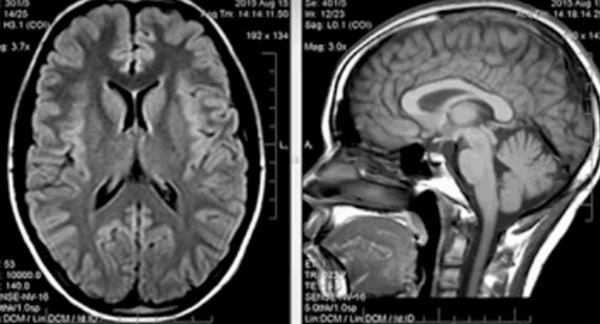

Прогрессирующий надъядерный паралич проявляется в виде нарушения взора вверх, экстрапирамидной симптоматики и умственных нарушениях. Заболевание развивается у лиц около 60 лет. Этиология неизвестна, почти все случаи спорадические. Частота 1-1,5 случаев на 100 тыс. населения. Заболевание характеризуется патологическим скопление в головном мозге тау-протеина. При МРТ головного мозга наблюдается диффузная атрофия, причем на сагиттальных Т1-взвешенных МРТ отмечается характерный симптом “пингвина”. Атрофические изменения моста и среднего мозга приводят к расширению водопровода и III желудочка, контур которых напоминает очертания пингвина.

![progressiruyushhij-nadyadernyj-paralich]()

МРТ головного мозга. Т12-взвешенная сагиттальная МРТ. Прогрессирующий надъядерный паралич. Симптом “пингвина”.